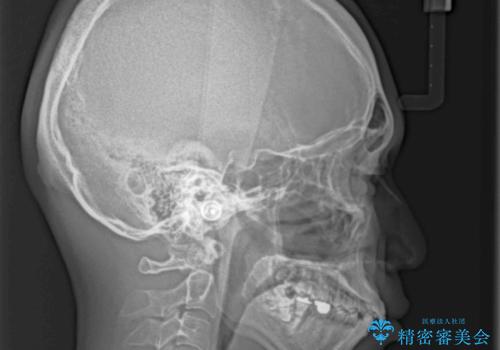

口が少し閉じにくい インビザラインによる非抜歯矯正

- 口元の突出感を治したいとのことで来院された患者様です。

上下顎ともにIPR(歯と歯の間を削る)と歯列全体の拡大によって口元が引っ込むように設計し、インビザラインにより治療を行うこととしました。

抜歯をして口元を下げなければならないほど出っ歯ではなかったため、少しずつ治療ゴールを変更しながら仕上げていきました。

気になっていた前歯の飛び出した印象は、最終的にはスッキリと引っ込み、大変満足していただきました。